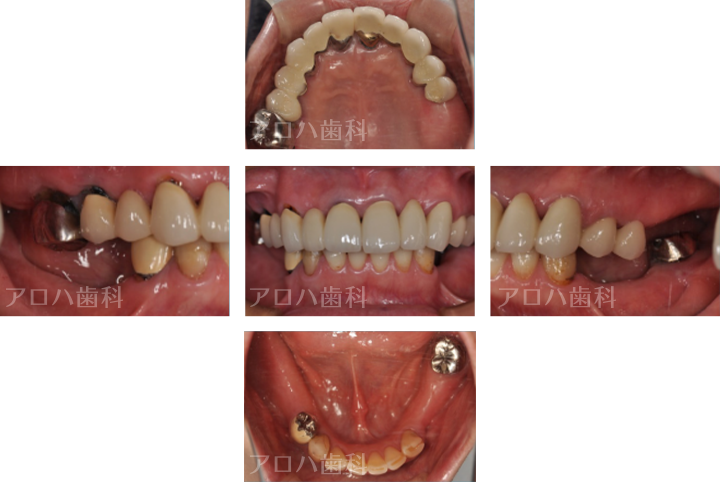

CASE01

初診時

治療終了後5年時

| 主訴 | 入れ歯をやり替えたい |

|---|---|

| 治療内容 | 上下顎とも状態が悪い歯を抜いて奥歯をインプラントで修復しました。 前歯は患者さまの希望のもとそのままにしています。 上顎は骨の高さが足りなかったため、【サイナスリフト】という特殊な手術を行い骨の高さを獲得しています。 術後経過もメインテナンスに通っていただいており、良好な状態を保っています。 |

| 治療期間 | 1年6ヶ月 |

| 治療費用 | 5,060,000円 |

| 費用詳細 | ・サイナスリフト(2か所) 660,000円 ・セデーション(静脈内鎮静法) 110,000円 ・TEC(仮歯) 220,000円 ・インプラント手術+アバットメント+上部構造(9歯) 3,960,000円 ・ポンティック(1歯) 110,000円 |